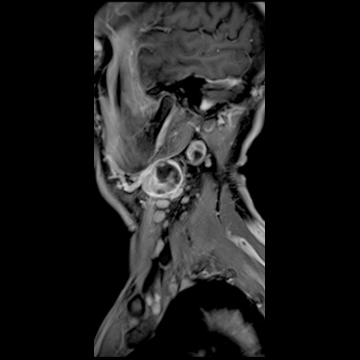

頚部腫瘍

- 造影3D VIBE

- 体動の影響を受けにくい